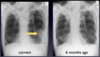

What is here ?

Left pneumonia has developed -lungs weird form childhood TB so differences from previous CXR useful